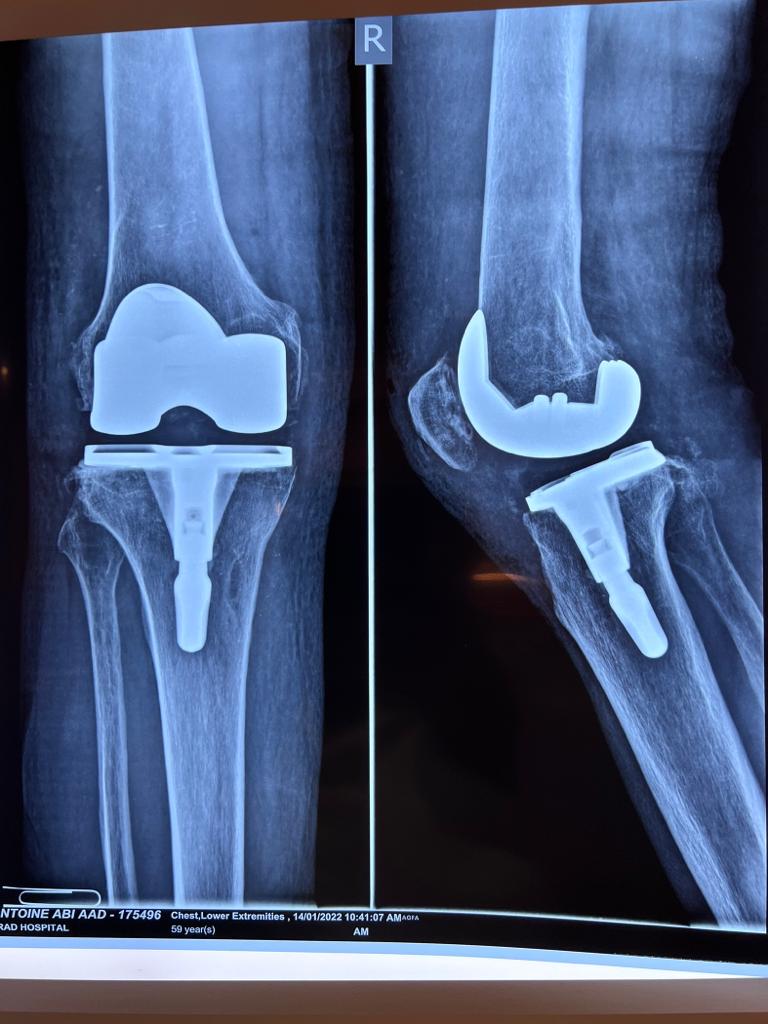

Total Knee Arthroplasty on a severe Genu Valgum

• Total Knee Arthroplasty on a severe Genu Valgum